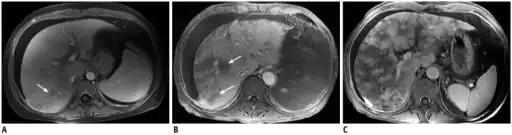

Doppler ultrasound of the liver is typically utilized to confirm or suggest the diagnosis. Common findings on liver doppler ultrasound include increased phasicity of portal veins with eventual development of portal flow reversal.

The liver is usually enlarged but maintained normal echogenicity. A liver biopsy is required for a definitive diagnosis.